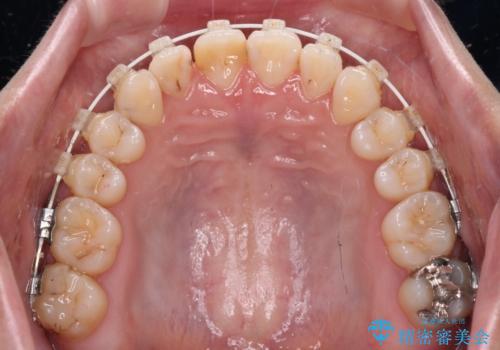

前歯のクロスバイトを治したい ワイヤー装置による矯正治療

- 前歯の反対咬合を気にして来院された患者様です。

マウスピース矯正も提案しましたが、しっかりと使用する自信がないとのことで、ワイヤー装置により矯正治療を行うこととしました。

クロスバイト改善まではスムーズに進みましたが、その後は強い舌の突出癖によりオープンバイトの期間が長く続きました。

舌のトレーニングをしっかりと実施してもらい、何とか仕上げることができました。